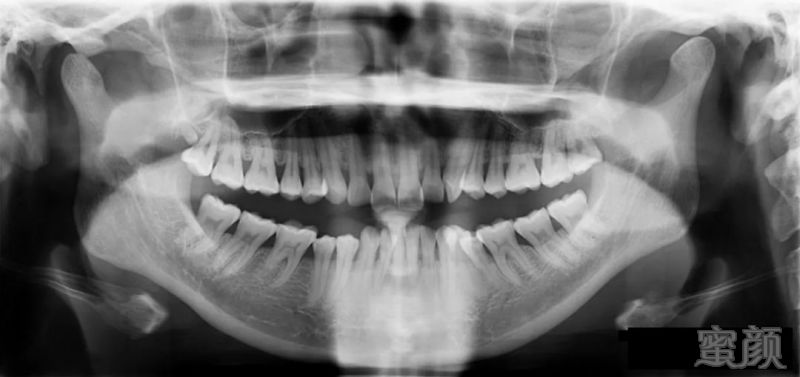

牙齿的 CT

商量方案时已经确定了至少要拔掉 1、2

颗牙,最终方案是选择了拔一颗,尽量把恢复期缩短。这里要表扬医生的医德和仁心,总是从病人的角度尽量多的考虑周全,体贴暖男!